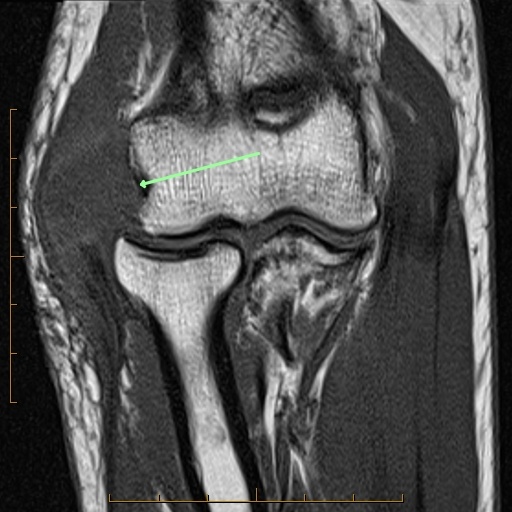

- Lateral capsule (torn-arrow, images two and three)

- Proper radial collateral ligament (torn-arrow, images two and three).